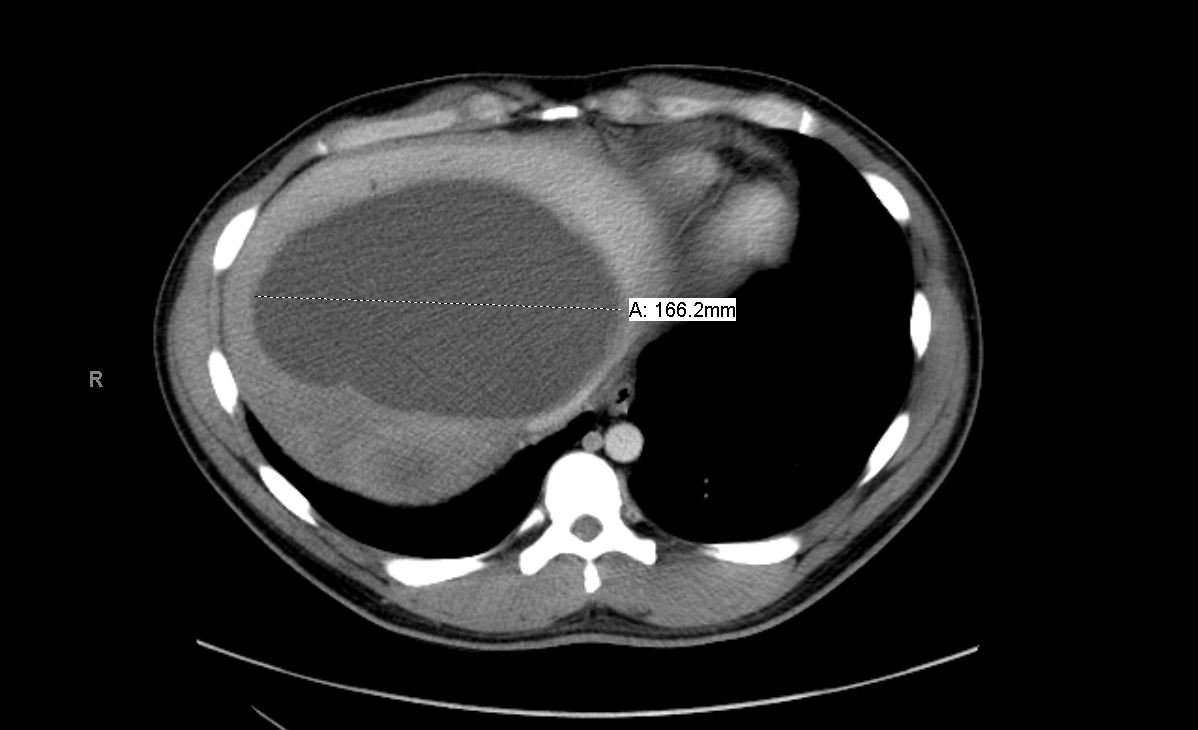

Although rare in the developed world, amebic infections are common worldwide and represent a challenging and often overlooked diagnosis. In this case, an amebic liver abscess was discovered in a 29-year-old male who presented to the emergency department (ED) complaining of right upper quadrant abdominal pain, weight loss, non-bilious/non-bloody vomiting, and diarrhea for three months. He recently traveled to India and Mexico. Point-of-care ultrasound discovered a liver mass and computed tomography (CT) confirmed the presence of a liver abscess. The case highlights the usefulness of ultrasound as an initial diagnostic tool, the importance of careful travel history in patients with suspected infectious diseases, and the initial provision of broad-spectrum coverage for bacterial and amebic pathogens for liver abscesses until the pathogen has been identified.